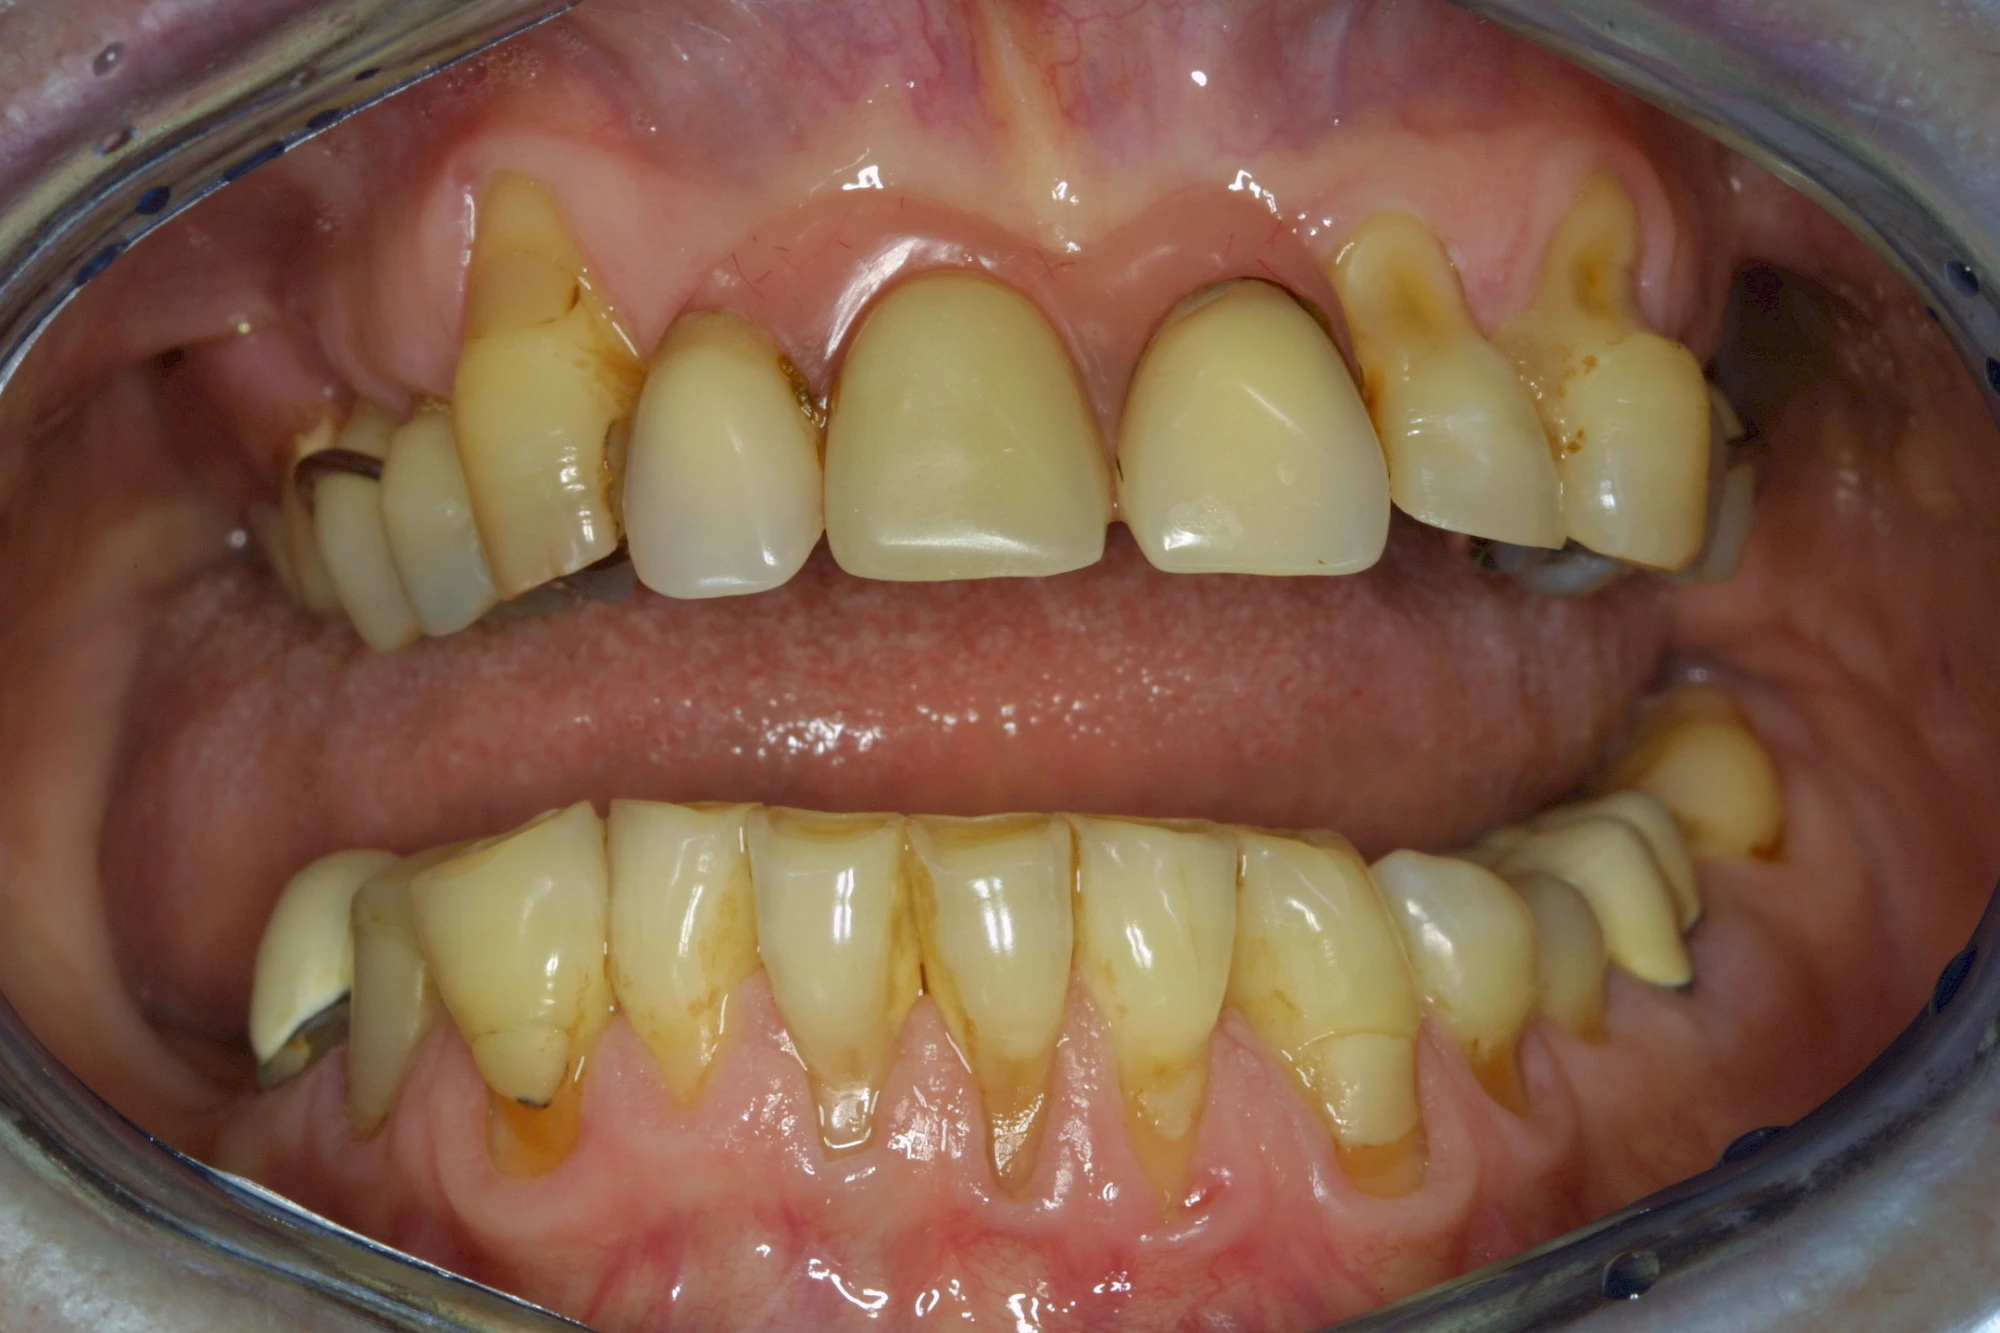

Auswaschung

Auswaschung (Erosion) dagegen ist eine Verschleißerscheinung der Zähne aufgrund von immer wiederkehrenden Säureangriffen durch die Nahrung, verstärkt zum Beispiel durch den Genuss säurehaltiger Getränke oder Speisen. Auch bei Menschen mit einer Essstörung (z. B. Bulimie) können die Zähne durch die Magensäure ausgewaschen erscheinen.